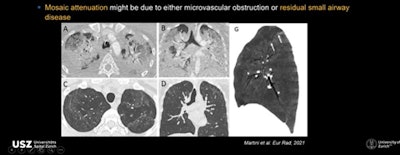

Another interesting three-month finding on CT is mosaic attenuation pattern with areas of hypoattenuation in patients who had severe or critical disease, noted Martini. This mosaic attenuation can be best visualized in minimum intensity projection (MIP) and might be due to either microvascular obstruction or residual small airway disease.

Revel, who presented, "What's the current role of imaging?" during the session pointed to mosaic attenuation as the most intriguing of the signs with its potential cause of small airway disease or vascular occlusion.

"I've noticed only the severe cases have the most abnormal total lung capacity (TLC) changes. I would suspect a vascular phenomenon rather than fibrotic changes -- which would affect the volumes. Only the diffusion capacity is abnormal," Revel noted.